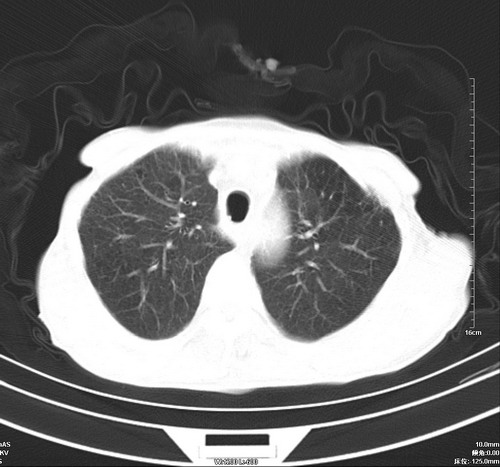

中后纵隔占位,气管、食道受压、变形、移位。恶性可能性大。

考虑:中后纵隔转移瘤可能性大,主动脉硬化。

中后纵隔占位, 考虑:转移瘤不除外.

1 气管旁、隆突下淋巴结明显肿大,肝左叶外侧段低密影,都考虑转移。

纵隔淋巴结肿大,考虑转移而来

肺癌,纵隔淋巴结转移,肝左叶病变考虑为转移病灶。

中后纵隔转移瘤可能性大,主动脉硬化。

中后纵隔转移瘤可能性大

后中纵隔团块影,伴气管、食道受压移位,首先考虑转移瘤,肝s5段低密度灶。建议增强检查,另外其结肠是否有问题请提供,右肺部分肺叶局限含气增多,考虑局限肺气肿。

建议强化检查,考虑纵隔型肺癌,小细胞可能性大。

后中纵隔团块影,伴气管、食道受压移位,首先考虑转移瘤,肝表现同11773。

后中纵隔淋巴结肿大,首先考虑转移瘤。